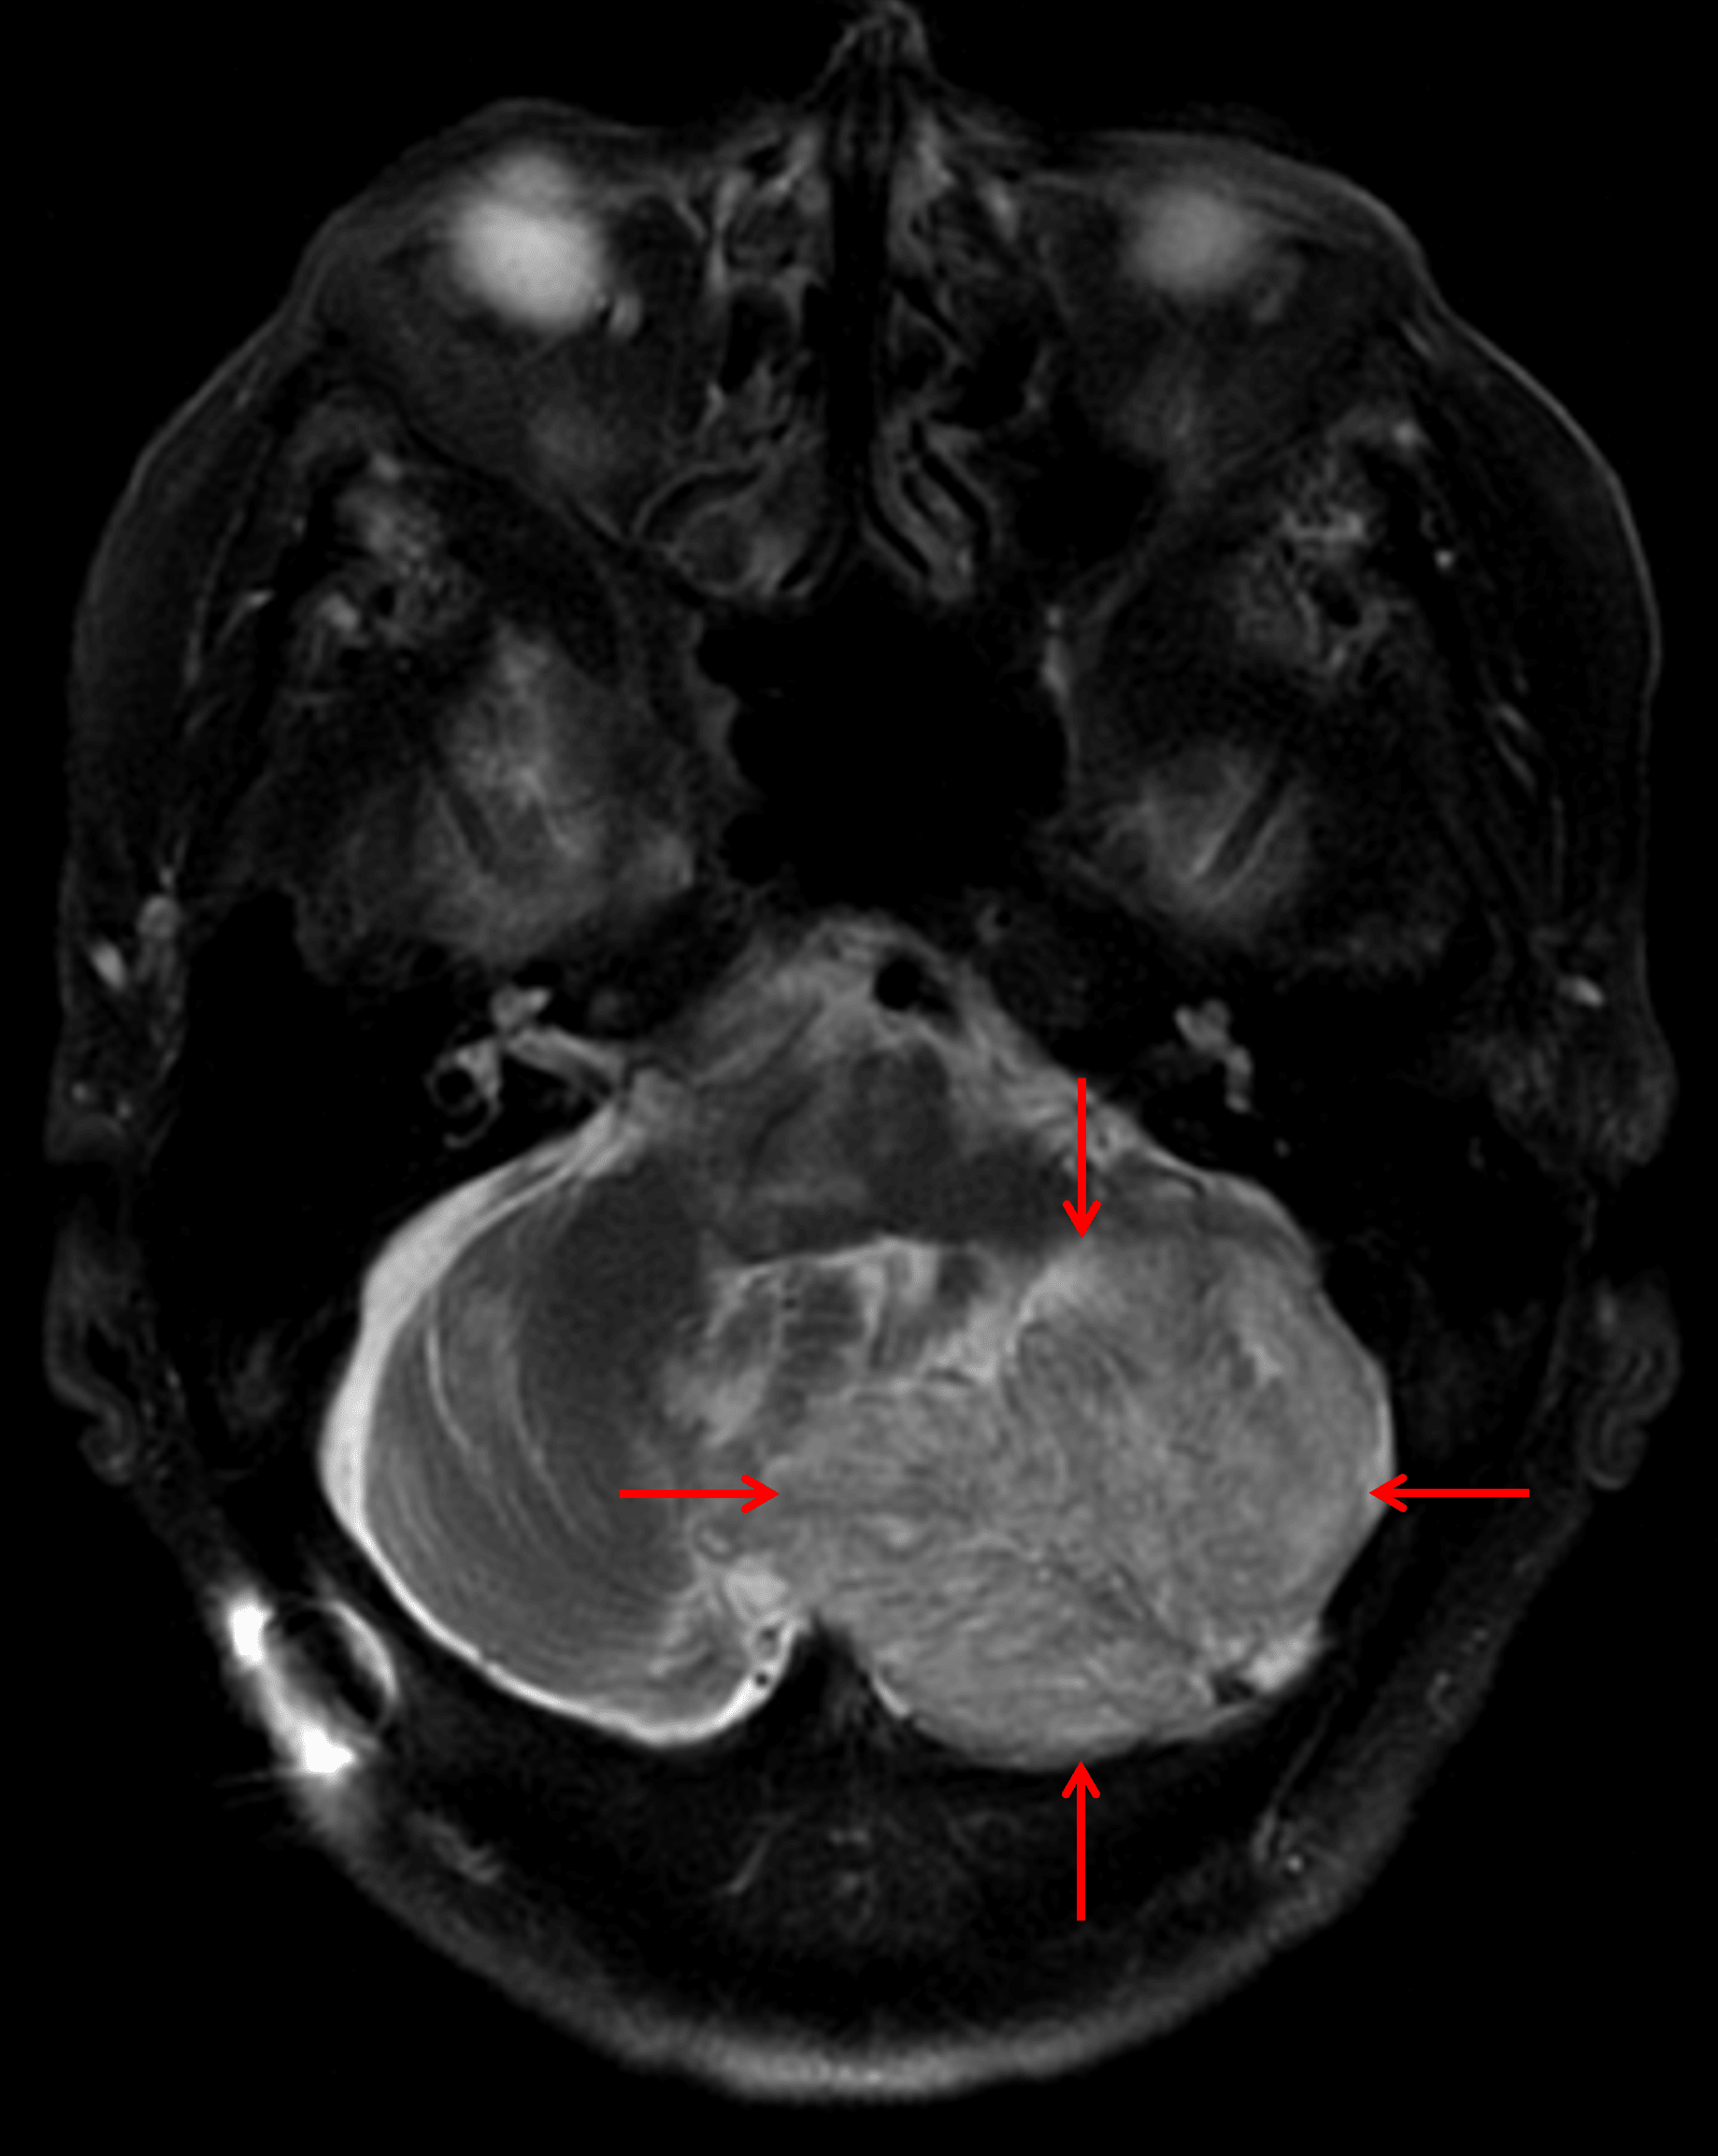

Annotated Images & Illustrations

Mildly T2 hyperintense left cerebellar mass with striated internal architecture (red arrows), which is a classic appearance for a dysplastic cerebellar gangliocytoma.

Dysplastic cerebellar gangliocytoma (Lhermitte Duclos disease)